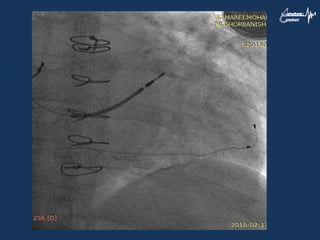

Case • A 73yr man was a case of ischemic cardiomyopathy with VT and LBBB • CRT-D was done successfully and there was improvement his heart failure • There was LV lead dislocation after two yeras

• 62.

• 63.

• 64.

• 65.